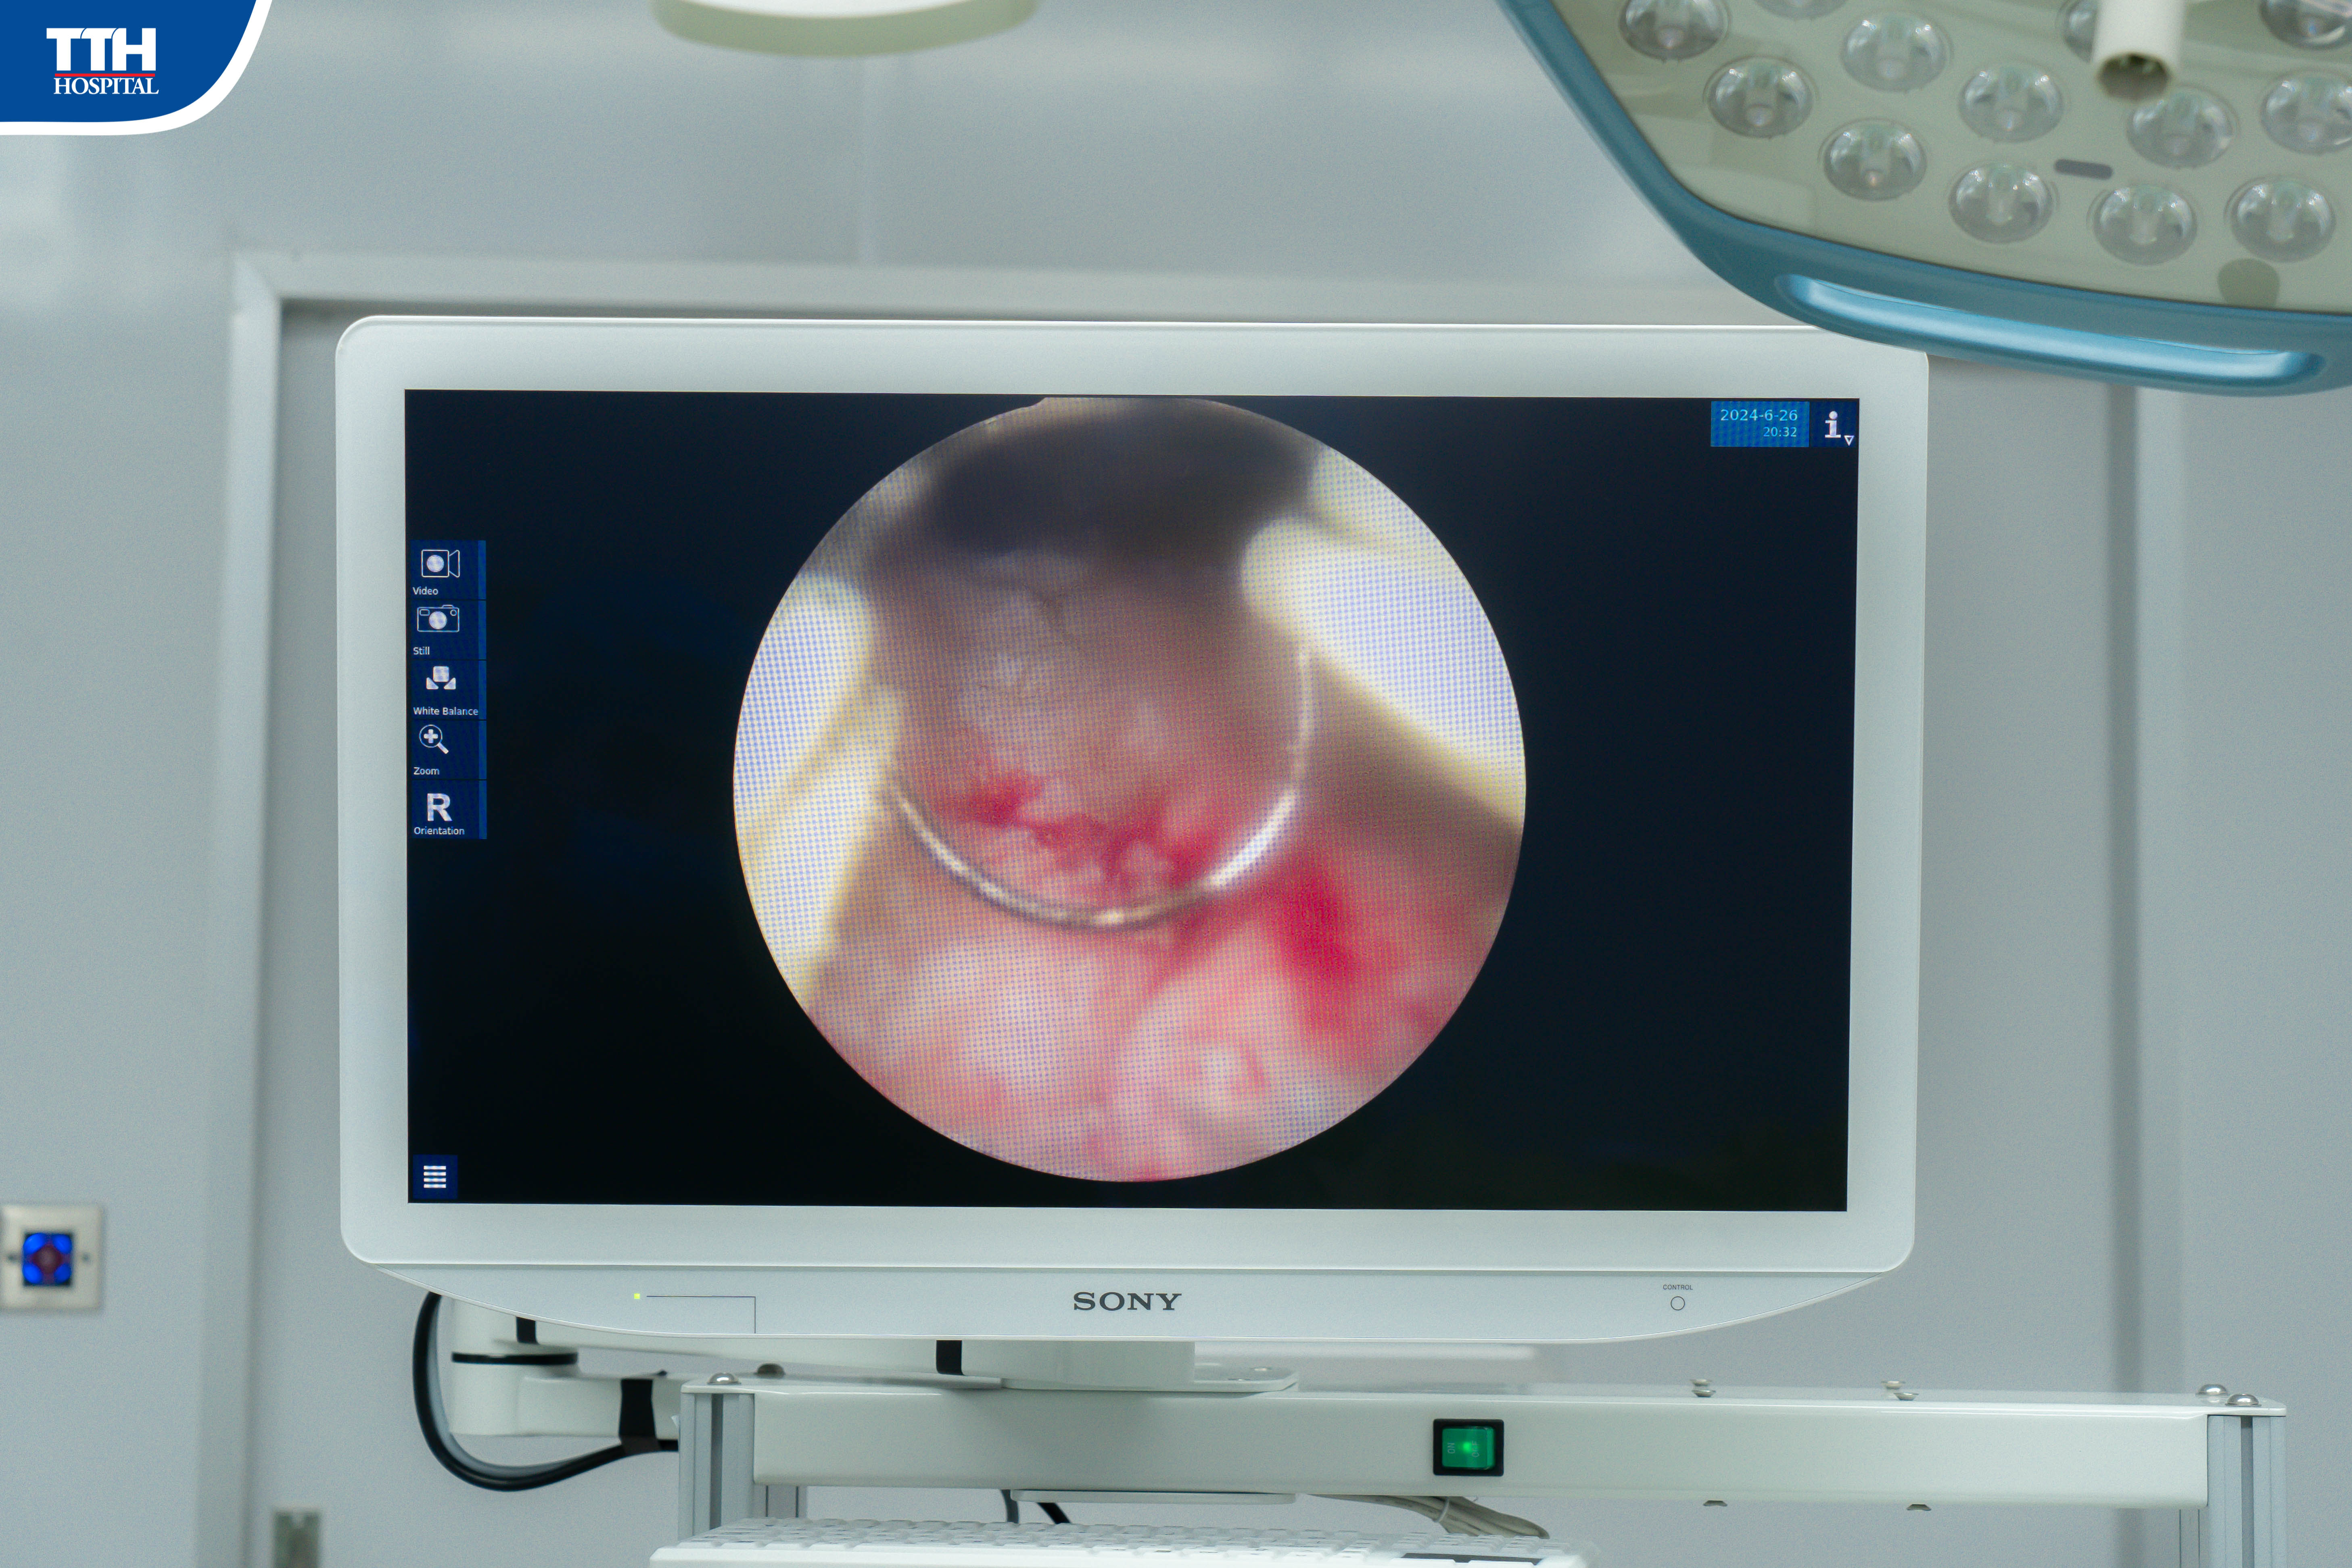

Vừa qua, khoa Ngoại Tổng hợp Bệnh viện Đa khoa TTH Quảng Bình vừa phẫu thuật nội soi cắt đốt tiền liệt tuyến qua đường niệu đạo giải quyết bí tiểu đồng thời chẩn đoán và điều trị kịp thời ung thư tiền liệt tuyến thành công cho bệnh nhân lớn tuổi. Theo đó, bệnh nhân K.N.C (88 tuổi, Lệ Thủy) tiểu khó, tiểu yếu đã lâu, nhiều lần bí tiểu có điều trị nhưng không đỡ nay bí tiểu tiếp nên nhập viện điều trị.

Nghi ngờ ung thư tiền liệt tuyến nhưng bệnh nhân lại già yếu, sức khỏe kém, bí tiểu nhiều lần nên bệnh nhân được bác sĩ chỉ định phẫu thuật nội soi cắt tiền liệt tuyến giải quyết bí tiểu đồng thời lấy mẫu làm giải phẫu bệnh. Kết quả sinh thiết sau đó khẳng định bệnh nhân ung thư tuyến tiền liệt và bệnh nhân được chỉ định cắt tinh hoàn 2 bên nhằm giảm ảnh hưởng của Testosterone giúp triệt căn ung thư tiền liệt tuyến.